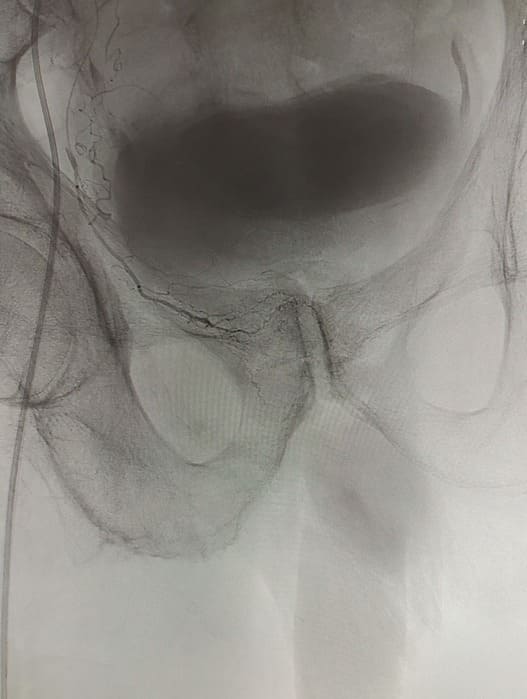

Зазвичай люди літнього віку мають вражені атеросклерозом та звивисті, внаслідок гіпертонічної хвороби судини. Цей випадок не був виключенням, тому нам довелося докласти максимум зусиль, використати високотехнологічне обладнання та інструменти, щоб віднайти цільові судини. На диво, незважаючи на попередню операцію, судинний малюнок рецидивної простати збігався з тим який буває у не оперованих пацієнтів. Тому нам вдалося їх чітко визначити з обох сторін та заповнити емболами. Це доволі кропітка праця, адже щоб викликати ішемію, необхідно поступово виключити кровоплин в усій тканині залози. Полегшувало операцію лише відсутність перетоків артерій на сусідні органи. Це дозволило нам безпечно емболізувати, не боячись негативних наслідків та ускладненнь.

Операція була виконана 28.05.2021. під місцевою анестезією, доступом через прокол в правій стегновій артерії. Вже на протязі тижня зменшилась кількість походів в туалет по маленькому (вночі до 1 разу), полегшилось сечовиділення та покращилось самопочуття хворого.